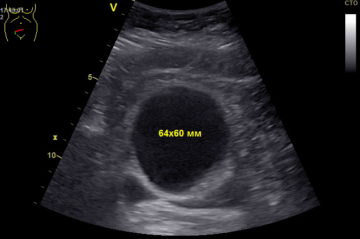

анэхогенным содержимым что это

С анэхогенным содержимым что это 87 фотографий